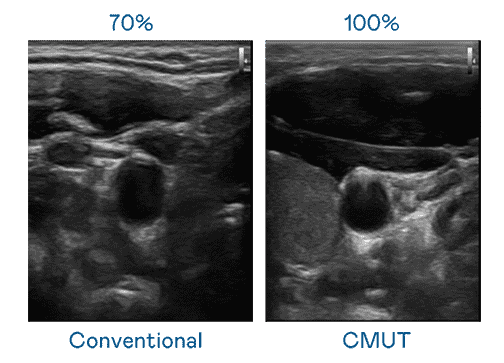

CMUT 技术是一种用电容式微机电元件来产生超音波讯号的技术。。。。与传统 PZT 压电式技术相比,,CMUT 频宽增加 30%,,,,更宽频的超音波讯号让影像解析度大幅提升,,,,是实现高影像品质医疗超音波扫描、、、、促进精准医疗发展的关键技术。。。

大频宽带来超清晰影像

超音波影像的解析度高低,,,,首先取决于探头能发出的讯号频宽。。。。菠菜论坛 CMUT 可提供高清晰的超音波讯号,,,,提供高频宽、、、高灵敏度、、影像纹理细节更高的超音波影像,,,,协助医护人员缩短影像判读时间及利用精准的医疗影像进行诊断。。。。